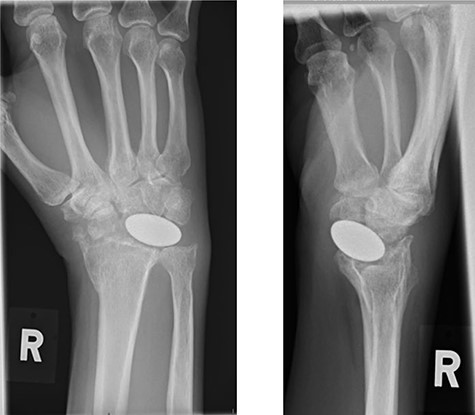

Radiographs demonstrated that the Pyrocarbon implant was palmarly displaced and rotated 90 degrees; it had migrated into the carpal tunnel/ distal forearm (Fig. 2). The clinical diagnosis was compression of the ulnar due to the migration of implant. Surgery was carried out 1 month later during which the Pyrocarbon Amandys wrist implant was removed through a volar approach (Fig. 3) and total wrist fusion was performed using a straight Arbeitsgemeinschaft für Osteosynthesefragen (AO) wrist fusion plate (Fig. 4). The surgery successfully relieved all wrist pain and was accompanied by prompt resolution of symptoms of ulnar nerve compression; she was discharged from follow-up approximately 3 months after surgery.

Intra-operative clinical photographs of the migrated pyrocarbon implant.